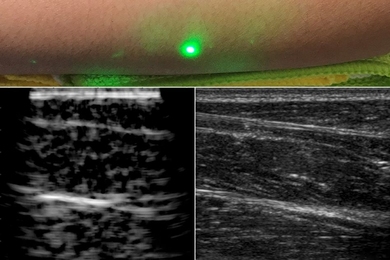

MIT researchers have developed a new non-invasive, hands-off medical imaging technique, reports Andrew Liszewski for Gizmodo. “Using lasers, they can peer beneath the surface of the skin without any physical contact required, improving upon the limitations of equipment like ultrasound machines,” Liszewski explains.